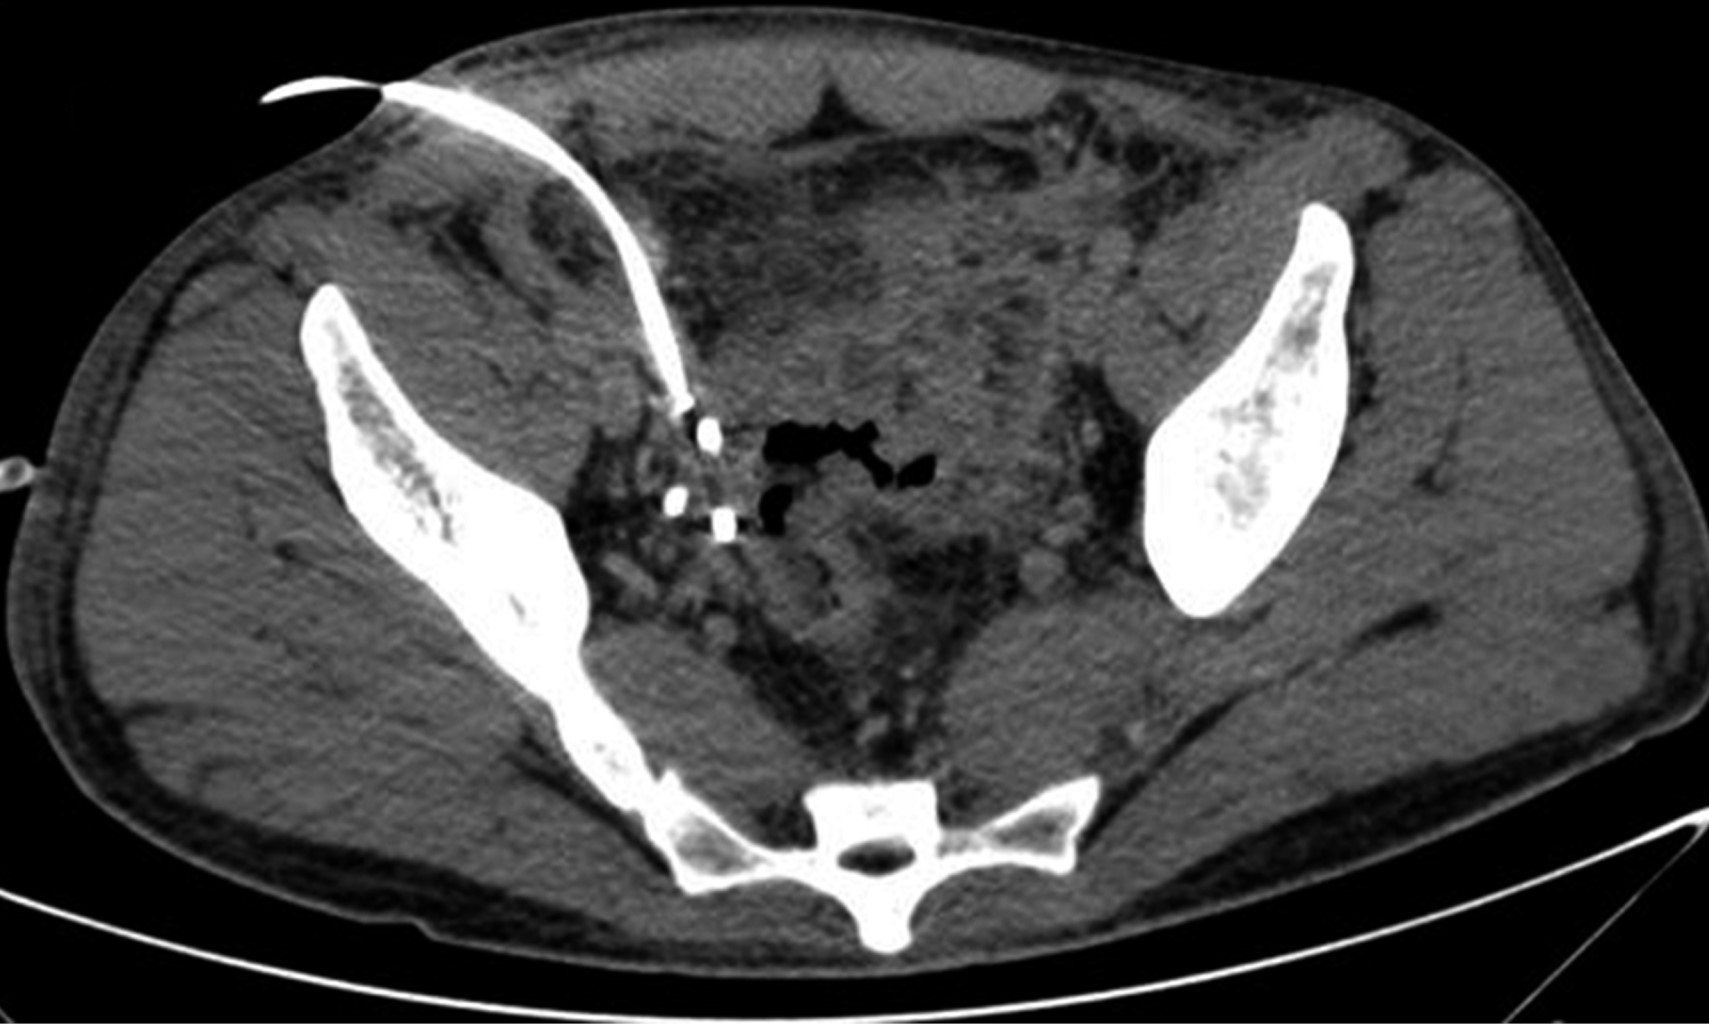

The CT scan of abdomen and pelvis with IV contrast showed free fluid in the right parieto-colic, intestinal interloop and peri-cecal slides. The cecal appendix with a diameter of 14 mm and thickening and enhancement of its wall was seen. A supra-vesical collection with extension to the right iliac fossa measuring 55 × 75 × 41 mm with a calculated volume of 88 cm3 (Figure 1) and another in the cul-de-sac with extension to the left iliac fossa measuring 60 × 57 × 70 mm with a volume of 125 cm3 were observed. Ultrasound-guided puncture with tomographic control of both collections was decided to perform (Figure 2), draining 70 and 120 cm3 of purulent fluid, respectively. Two Dawson Mueller® 10.2 Fr drains were left, one in the right iliac fossa and the other in the cul-de-sac zone. Broad spectrum antimicrobial management was started with meropenem 1 g iv every eight hours and vancomycin 1 g iv every 12 hours. He was left fasting for two days and parenteral nutritional support was started for three days with Oliclinomel® solution. The aerobic culture grew Streptococcus constellatus sensitive to ertapenem, so antimicrobial coverage was changed to ertapenem 1 g iv every 24 hours and vancomycin. The patient remained clinically stable, with no evidence of systemic inflammatory response and a progressive decrease in abdominal pain intensity. A control CT scan on his third hospital day (Figure 3) showed a significant decrease of fluid inside the collections. The right drain was removed on fourth day, with a total output of 10 cm3. Inflammatory markers showed a progressive decrease during his hospital stay. Final lab test results showed a white blood cell count of 9.9 10?3/μl, segmented neutrophils 67%, band forms 0% and a CRP of 4.05 mg/dl. The left drain was removed prior to hospital discharge on the ninth day of stay with a total output of 82 cm3. No interval appendectomy was performed during his follow-up because, based on age, history and imaging studies at diagnosis, the probability of neoplasia was considered low according to existing literature recommendations.

Figure 2